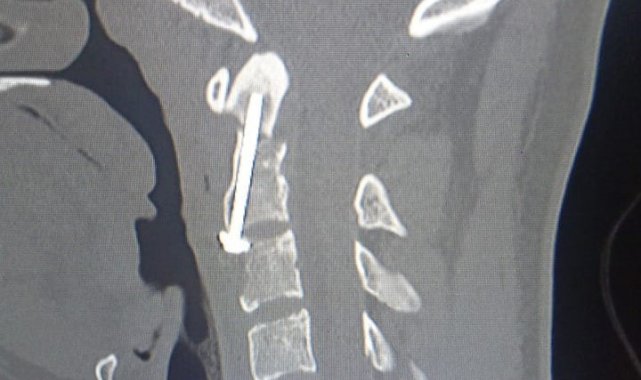

Ordu'da geçirdiği motosiklet kazası sonucu ağır yaralanan 20 yaşındaki genç, gerçekleştirilen nadir ve kritik bir cerrahi müdahale ile sağlığına kavuştu. Genç hasta, hastaneden yürüyerek taburcu edildi.Ordu'da 17 Mayıs 2025 tarihinde gerçekleşen trafik kazasında Medical Park Ordu Hastanesi'ne getirilen Şimal Öktem'in yapılan tetkiklerinde, boyun omurga bölgesinde hayati tehlike arz eden bir odontoid (dens) kırığı tespit edildi. Hastanedeki tetkiklerde 20 yaşındaki Öktem'in vücudundaki kırıkların, omuriliğe zarar vererek felç veya ölüm riski oluşturabilen, üst servikal travmalar arasında yer alan yüksek enerjili kırıklar olduğu anlaşıldı."Ameliyatta özel bir teknik uygulandı"Şimal Öktem'in kırığının, tıpta 'Tip 2 odontoid kırığı' olarak sınıflandırılan ve nadir görülen bir durum olduğunu dile getiren Medical Park Ordu Hastanesi Beyin ve Sinir Cerrahisi Uzmanı Dr. Öğr. Üyesi Ahmet Serhat Eroğlu, hastanın kritik durumuyla ilgili "Hastamızın boyun kırığı titizlikle planlanması gereken bir cerrahi gerektiriyordu. Omurilik fonksiyonlarının korunması için odontoid vida tespiti ameliyatı gerçekleştirdik. Bu ameliyat, kırığın konumu itibarıyla özel bir teknik olan anterior odontoid vidalama yöntemiyle yapıldı ve Ordu'da ilk kez uygulandı. Başarılı geçen operasyon sayesinde hastamızın omurilik fonksiyonları korunarak iyileşme süreci hızla ilerledi" dedi."Hastamız kısa sürede sağlığına kavuştu"Hastanın ameliyat sonrası 1 gece yoğun bakımda yakından izlendiğini belirten Dr. Eroğlu, ertesi gün servise alınarak yürütülen genç hastanın hızla toparlandığını ifade etti. Dr. Öğr. Üyesi Eroğlu, "Boyun omurga kırıkları, özellikle odontoid kırıkları, erken teşhis ve hızlı cerrahi müdahale gerektirir. Bu ameliyat, Ordu'da ilk kez gerçekleştirilmesi açısından büyük önem taşımaktadır. Ekip çalışması ve multidisipliner yaklaşım sayesinde hastamızın sağlığına kavuşması bizleri çok mutlu etti. Bu başarı, modern tıbbın ve ileri cerrahi tekniklerin bir sonucudur" diye konuştu.Tedavisi yapılan Şimal Öktem, kısa sürede sağlığına kavuşarak hastaneden yürüyerek ayrıldı.